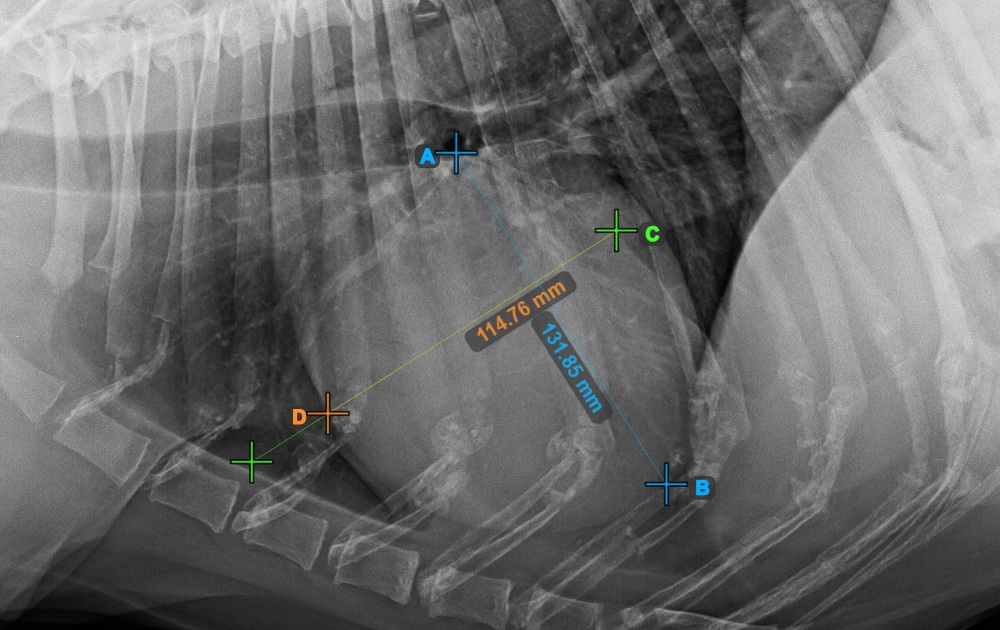

Vervollständigen Sie die Kurzachse des Herzens, indem Sie den breitesten linken (hinteren) Punkt markieren.

Das Bild unten zeigt die typische Platzierung des hintersten Punkts auf der Kurzachse des Herzens.